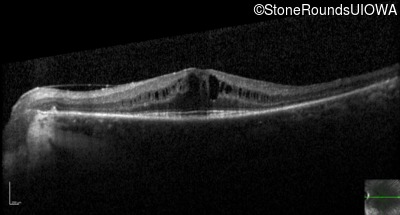

Optical Coherence Tomography - Left - 20/30 +2

Exemplar / OCT Stack

OCT Stack